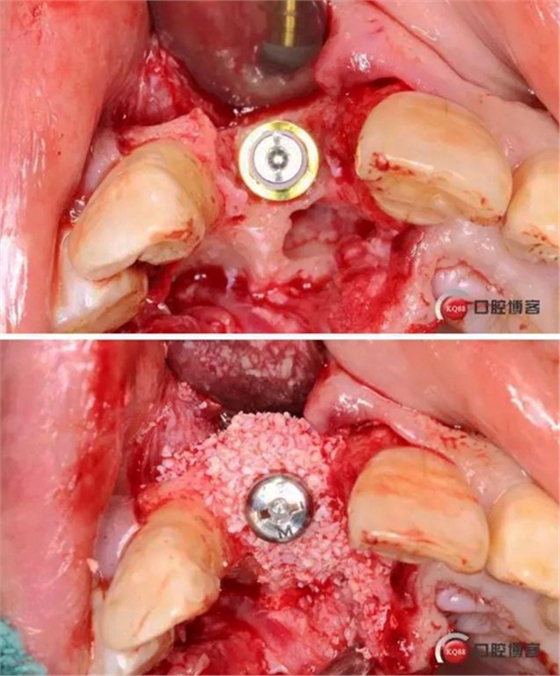

術中照

術后縫合